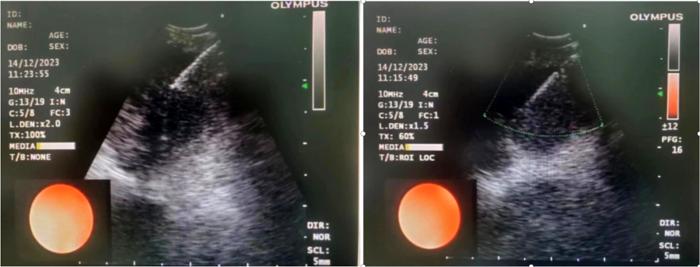

患者,女,72歲,2月來“反復咳嗽、咳痰,偶咳白痰中帶血絲”,胸部CT提示“肺占位、肺炎”,收住院。完善胸部強化CT提示“左肺占位、肺炎、縱膈多發(fā)淋巴結腫大”,電子支氣管鏡檢查見左肺上葉支氣管血塊及壞死物阻塞,清除后見管腔通暢,刷檢DNA細胞學示“細胞退變明顯,建議進一步檢查”。10月27日行CT引導下肺穿刺活檢,病理示“機化性肺炎”,給予抗感染及激素治療,患者癥狀好轉出院。半月前,患者復查肺CT發(fā)現(xiàn)病灶較前稍有增大,張強主任考慮患者癥狀雖有好轉,但仍存在腫瘤性病變可能性。經(jīng)過討論及與患者家屬充分溝通后,決定實施支氣管內超聲引導下針吸活檢術(EBUS-TBNA)+電子支氣管鏡檢查+現(xiàn)場快速評價(ROSE)技術,以提高診斷陽性率。術中ROSE提示查找到可疑癌細胞,取材量較足分。最后病理檢查明確診斷為低分化肺腺癌,隨后進行基因檢測,明確了治療方向。

患者,男,70歲,近2個月來“活動后呼吸困難,近日又出現(xiàn)痰中帶鮮血”,收住院。胸部增強CT見“左肺下葉外周型占位,肺門、縱膈淋巴結腫大”。張強主任帶領團隊討論分析患者病情,高度懷疑為腫瘤性病變,且普通電子支氣管鏡獲取組織困難,病變緊貼主動脈,經(jīng)皮肺穿刺活檢風險大。為明確診斷及分期,決定為患者實施支氣管內超聲引導下針吸活檢術(EBUS-TBNA)+電子支氣管鏡下病灶活檢+現(xiàn)場快速評價(ROSE)。術中ROSE快速診斷查找到肺腺癌細胞,手術過程順利。最后病理檢查明確診斷為肺腺癌,為患者的下一步治療確定了方向。

支氣管內超聲引導下針吸活檢術,是一種在電子支氣管鏡前端安裝超聲探頭的設備,結合專用的吸引活檢針,可在實時超聲引導下對臨近氣管或支氣管的胸內病變進行活檢。該技術不僅能實時觀察到病灶,同時可幫助確認血管的位置,在提高穿刺診斷陽性率的同時防止誤穿血管,減少風險,術中ROSE進一步提高了取材效率,可實現(xiàn)精準、高效、安全的明確診斷,又可大大減少對患者的損傷。(于 雪)